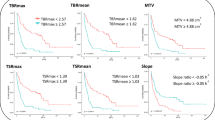

Although continuous measures of the change in FLAIR volume was not a predictor of OS in LGGs, grouping patients into those with increasing versus decreasing FLAIR volume stratified patients into short and long-term residual OS (Fig. 4a; Log-rank, P = 0.025, HR = 2.220). Similarly, patients with an increasing PET uptake had worse residual OS (Fig. 4b; Log-rank P = 0.0311, HR = 2.148). Additionally, patients with increasing rate of both FLAIR volume and PET uptake had significantly shorter OS compared to patients with decreasing FLAIR volume or PET uptake (Fig. 4c; Log-rank, P = 0.0135, HR = 2.354), suggesting the combination of both change in FLAIR volume and PET uptake may be meaningful for identifying patients at highest risk.

Kaplan–Meier plots showing significant differences in residual OS from the 2nd PET scan in patients with a a positive or negative rate of change in FLAIR volume (HR = 2.220, P = 0.025); b a positive or negative rate of change in PET uptake (HR = 2.148, P = 0.0311); and c patients with a positive rate of change in both FLAIR volume and PET uptake compared to those with either a negative rate in FLAIR volume or PET uptake changes (HR = 2.354, P = 0.0135). Black = positive rate of change or high risk. Gray = negative rate of change or low risk